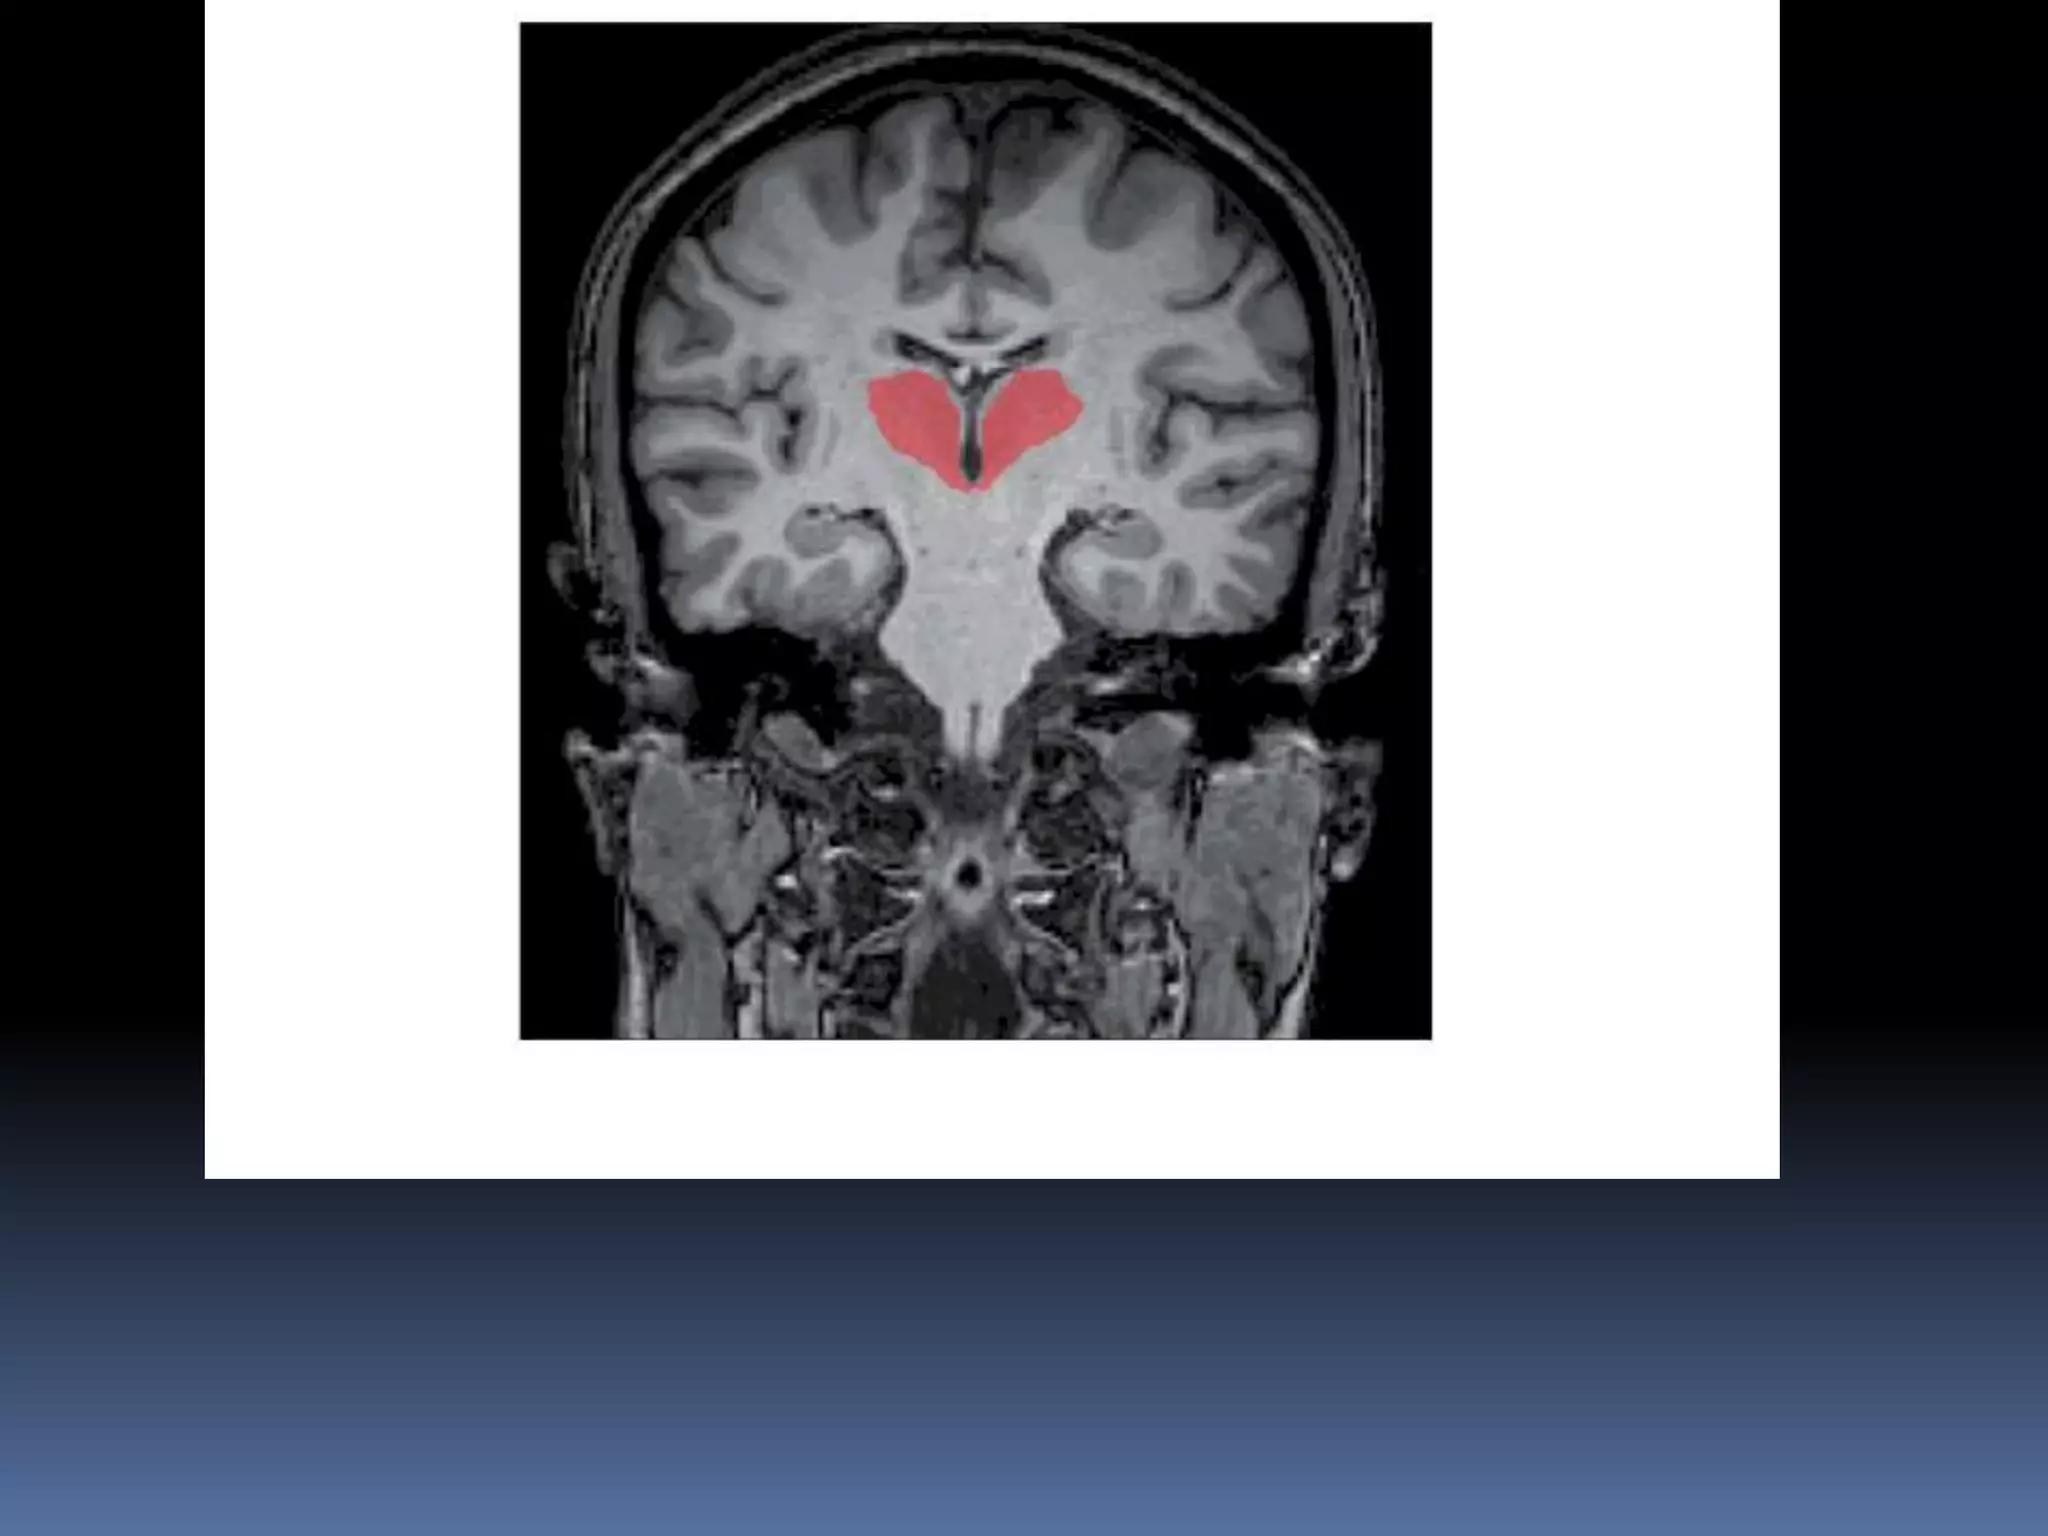

 divided into medial and lateral nuclear

groups by a thin curved sheet of myelinated

fibres called internal medullary lamina..

 It splits anteriorly to enclose a group of

nuclei, collectively called anterior nucleus,

which is close to interventricular foramen

 Medial group contains one large nucleus

called dorsomedial nucleus

 Lateral group is subdivided into a dorsal and

ventral tier

 Dorsal tier consists of lateral dorsal, lateral

posterior nuclei and pulvinar.